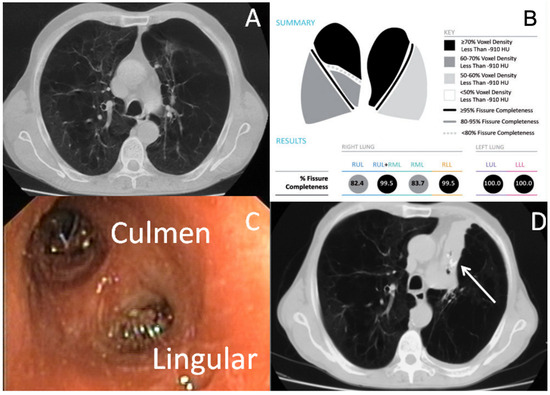

- Fiorelli, A.; Poggi, C.; Anile, M.; Cascone, R.; Carlucci, A.; Cassiano, F.; Andreetti, C.; Tiracorrendo, M.; Diso, D.; Serra, N.; et al. Visual analysis versus quantitative CT analysis of interlobar fissure integrity in selecting emphysematous patients for endobronchial valve treatment. Interact. Cardiovasc. Thorac. Surg. 2019, 28, 751–759. [Google Scholar] [CrossRef] [PubMed]

- Fiorelli, A.; Santini, M.; Shah, P. When can computed tomography-fissure analysis replace Chartis collateral ventilation assessment in the prediction of patients with emphysema who might benefit from endobronchial valve therapy? Interact. Cardiovasc. Thorac. Surg. 2018, 26, 313–318. [Google Scholar] [CrossRef] [PubMed]

- Fiorelli, A.; Petrillo, M.; Vicidomini, G.; Di Crescenzo, V.G.; Frongillo, E.; De Felice, A.; Rotondo, A.; Santini, M. Quantitative assessment of emphysematous parenchyma using multidetector-row computed tomography in patients scheduled for endobronchial treatment with one-way valves. Interact. Cardiovasc. Thorac. Surg. 2014, 19, 246–255. [Google Scholar] [CrossRef]